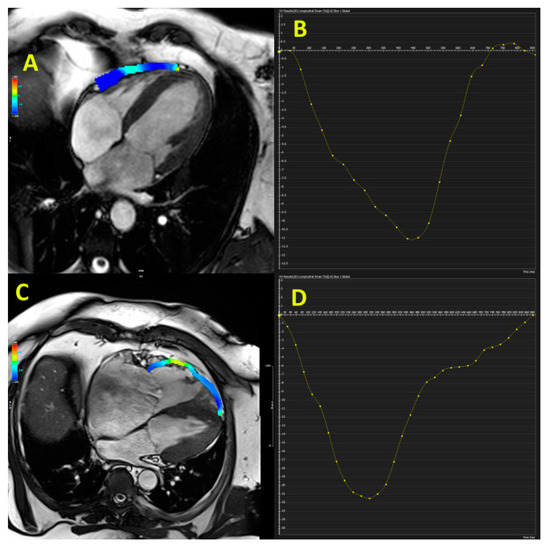

- Wu, R.; Shi, R.Y.; An, D.A.L.; Chen, B.H.; Jiang, M.; Bacyinski, A.; Han, T.T.; Deen, J.M.; Kaddurah, H.; Hu, J.; et al. Biventricular tissue tracking demonstrating associations between left ventricular myocardial extracellular volume, pulmonary artery pressure, and reduced right ventricular ejection fraction in patients with systemic lupus erythematosus using cardiovascular MRI. Clin. Radiol. 2020, 75, 237. [Google Scholar] [PubMed]